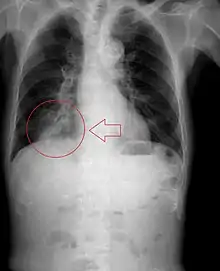

Radiography is the most common form of imaging used in the initial assessment of a foreign body presentation. Most patients receive a chest x-ray to determine the location of the foreign body.[2] Lateral neck, chest, and bilateral decubitus end-expiratory chest x-rays should be obtained in patients suspected of having aspirated a foreign body.[6] However, the presence of normal findings on chest radiography should not rule out foreign body aspiration as not all objects can be visualized.[2] In fact, up to 50% of cases can have normal findings on radiography.[7] This is because visibility of an object depends on many factors, such as the object's material, size, anatomic location and surrounding structures, as well as the patient's body habitus.[13] X-ray beams only show an object if that object's composition blocks the rays from traveling through, making it radiopaque and appearing lighter or white on the image. This also requires it to not be stuck behind something that blocks the beams first.[13] Objects that are radiopaque include items made of most metals except aluminum, bones except most fish bones, and glass. If the material does not block the x-ray beams it is considered radiolucent and will appear dark which prevents visualization.[13] This includes material such as most plastics, most fish bones, wood, and most aluminum objects.[13]

Signs on x-ray that are more commonly seen than the object itself and can be indicative of foreign body aspiration include visualization of the foreign body or hyperinflation of the affected lung.[13] Other x-ray findings that can be seen with foreign body aspiration include obstructive emphysema, atelectasis, and consolidation.[8]

While, x-ray can be used to visualize the location and identity of a foreign body, rigid bronchoscopy under general anesthesia is the gold-standard for diagnosis since the foreign body can be visualized and removed with this intervention.[2] Rigid bronchoscopy is indicated when two of the three following criteria are met: report of foreign body aspiration by the patient or a witness, abnormal lung exam findings, or abnormal chest x-ray findings.[2]